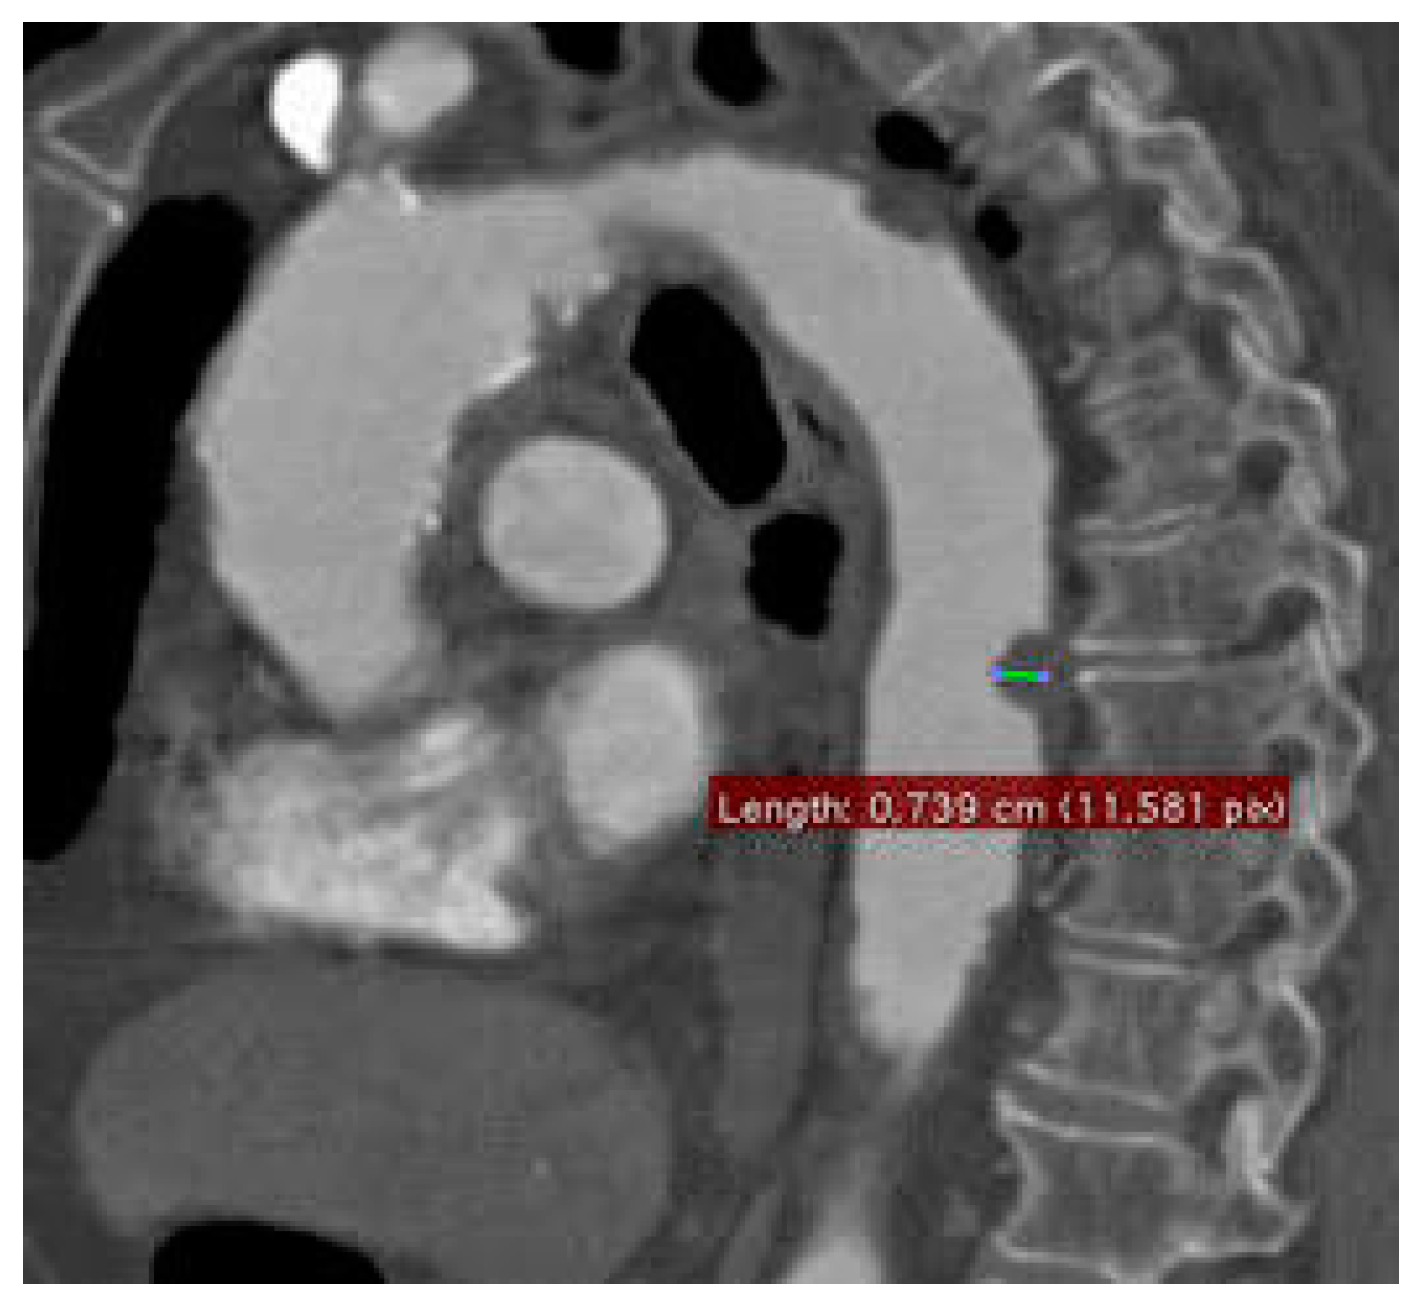

Single-Center Experience with Simultaneous Mural Aortic Thrombosis and Peripheral Obstructive Disease in Pre-COVID-19 and COVID-19 Era

3. Results